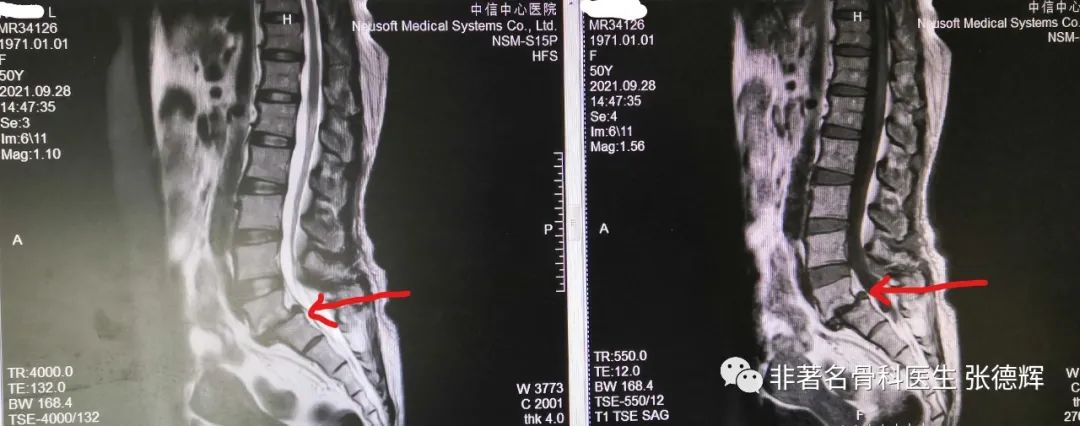

腰椎核磁共振检查提示:腰5骶1滑脱,硬膜囊明显受压迂曲变形

腰5骶1椎间隙明显变窄